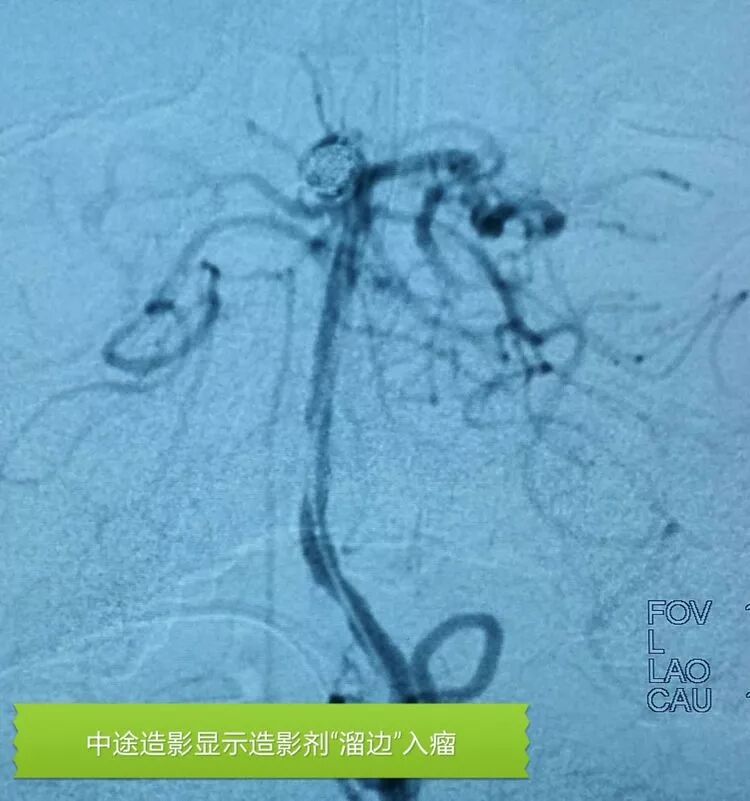

基底动脉顶端微小动脉瘤,是个有欺骗性的病例。从下面这个角度的造影看,瘤体长轴跟基底动脉主干平行,似乎用直头微导管栓塞即可

但从侧位造影和CTA观察,其实瘤体长轴还是跟基底动脉主干有成角的。这家医院的DSA机器没有三维重建工作站,只能参考CTA

于是我们把微导管头塑成S形

顺利完成该动脉瘤的栓塞。所以,要多角度观察动脉瘤跟载瘤动脉的解剖走行,即使硬件上没有三维工作站,咱们头脑中也要有立体构象,不要一叶障目,被狡猾的敌人所欺骗